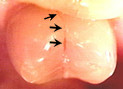

cracked toothCracked tooth. When a tooth is cracked, a filling will not seal the crack. A crown has to be placed over the tooth to hold it and the crack together. If a crown is not placed on the tooth, the tooth will become sensitive to chewing pressure, or will eventually break. It is important to crown a cracked tooth before it breaks, because in some cases a broken tooth cannot be crowned and must be extracted.